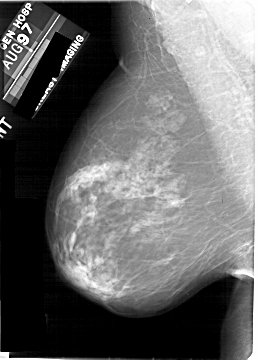

A_1924_1.RIGHT_CC

RIGHT_CC LINES 5266 PIXELS_PER_LINE 3166 BITS_PER_PIXEL 12 RESOLUTION 43.5 OVERLAY

FILE: A_1924_1.RIGHT_CC.OVERLAY

TOTAL_ABNORMALITIES 1

ABNORMALITY 1

LESION_TYPE CALCIFICATION TYPE PLEOMORPHIC DISTRIBUTION CLUSTERED

ASSESSMENT 4

SUBTLETY 4

PATHOLOGY BENIGN

TOTAL_OUTLINES 1

BOUNDARY